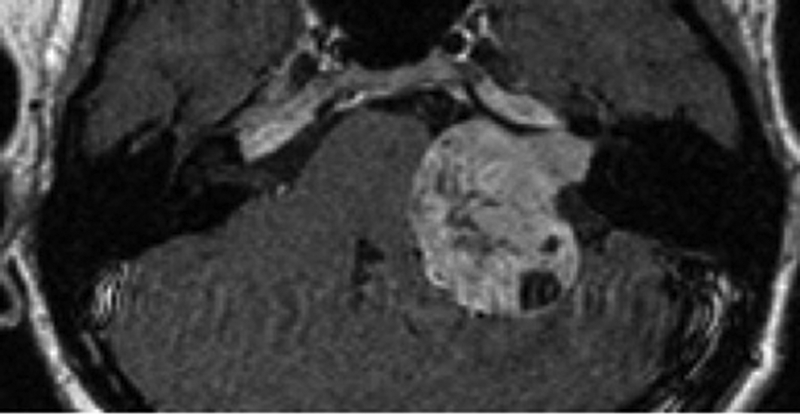

The presence of additional asymmetric or unilateral sensorineural hearing loss should certainly prompt investigation for a CPA or IAM mass lesion (Figure 1). The degree of asymmetry in hearing thresholds required to trigger imaging has been much studied, and 15-20 dB difference (either over a range or at specific or averaged frequencies) is generally proposed for the best compromise of sensitivity in screening rates [5, 6].

Figure 1: Gadolinium enhanced axial T1-w image demonstrates left IAM and CPA vestibular schwannoma.